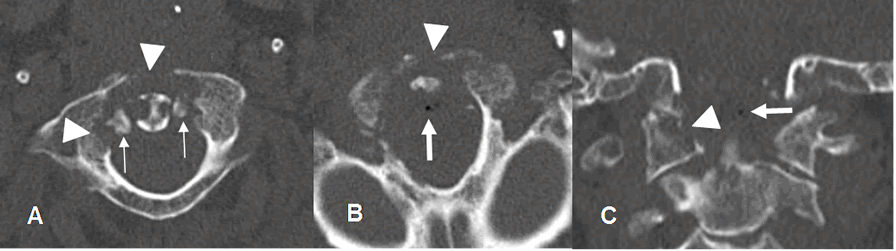

Fig 30 C. Osteomielitis aguda.

A y B: TAC axial. C: TAC reconstrucción coronal. Igual paciente anterior. Mala evolución clínica, con fiebre y sepsis. En el TAC de control se encuentra osteolisis del arco anterior y el lado derecho de C1 y la odontoides, por osteomielitis. (Puntas de flecha). Hay fragmentos óseos libres dentro del canal. (Flechas delgadas). Adicionalmente existen burbujas de aire dentro del canal, por la formación de absceso. (Flechas gruesas).